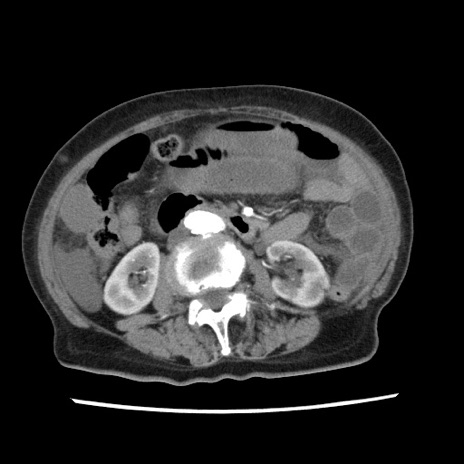

冠状断像

【症例】80歳代女性

【主訴】腹痛

【現病歴】8時間前から腹痛あり来院。

【既往歴】糖尿病、脂質異常症、子宮体癌にて子宮全摘術

【身体所見】意識清明・会話良好だが腹痛で苦悶様、全腹部にわたって反跳痛と圧痛あり

【データ】WBC 13600、CRP 0.14、LDH 224、CK 90